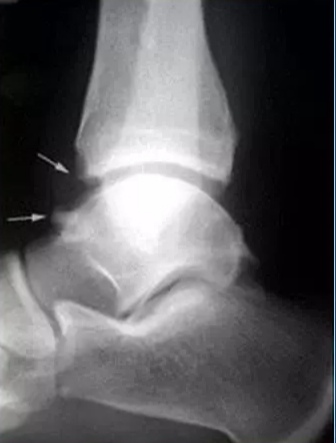

在多达60%的职业足球运动员中,可以发现胫骨以及距骨的骨赘。 这些骨赘并不总是引起症状,但是它们是前踝撞击的重要组成部分,而且常常可以作为前踝撞击的诊断依据。从简单的侧位X线片上可以看见胫骨前方的骨赘以及相应位置的距骨骨赘。关于这些骨赘的起源有多种假说。McMurray首先提出了一种假说,他认为这些骨赘的产生是由于关节囊和韧带在跖屈的时候被反复牵拉。根据他的假说,这些增生都是位于关节囊的附丽点。近年的一些文献也报道这些附丽点附近的增生位于距骨的外侧面。但是,另外一些文献则显示这些增生与踝关节前关节囊无关。骨赘被认为是在关节囊内产生的,在关节软骨的边缘发生骨赘增生过程。慢性的软骨边缘损伤导致软骨增生,瘢痕形成,最后形成这些骨赘。这种软骨边缘的损伤可能源自多种受伤类型。例如,在旋后性创伤中,软骨边缘的损伤来自受伤当时的胫骨与距骨的撞击,这可能导致骨赘增生,特别是这种创伤过程再次发生的时候。 强力的背伸以及多次反复的直接微小创伤也会导致软骨边缘的损伤。

距骨的骨赘最常见于中线的内侧,而胫骨的骨贅常见于中线的外侧,它们常常不会互相重叠。

前内侧撞击并不是慢性踝关节疼痛的常见原因,但是前内侧骨赘引起的撞击和踝关节疼痛可见于文献。骨赘源自前内凹,位于前踝向内踝移行部分,距骨穹隆、距骨体以及距骨颈的内侧向前内移行部分。在浅层,这个凹被前内踝关节关节囊包裹。慢性不稳定会导致反复的内翻性创伤,从而导致前内的骨性增生。这种反复的创伤会导致内侧退行性变,形成瘢痕组织,最后成为骨赘。